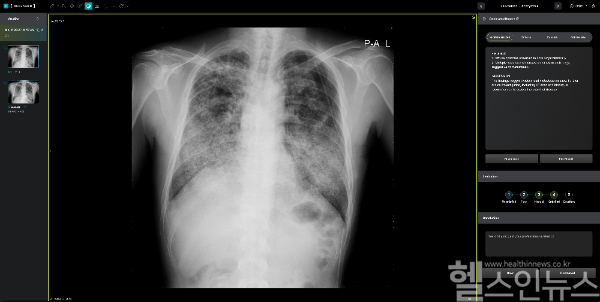

딥젠은 LLaMa, DeepSeek 등 여러 오픈소스의 장점을 선택적으로 적용한 의료 최적화 AI 서비스 플랫폼이다. 강화학습 및 기술증류의 장점을 지닌 딥시크 R1을 적용함으로써 추론 및 생성의 정확도를 높였다.

또, 기술 증류(Knowledge Distillation)를 통해 경량화된 딥젠을 구현한다. 고성능 AI 모델(Teacher Model)의 지식을 작은 AI 모델(Student Model)로 이전할 수 있어, 저사양 서버에서도 높은 정확도를 유지할 수 있도록 최적화한다. 병원마다 다른 IT 인프라 환경에서도 동일한 성능 구현이 가능해 클라우드 환경 및 다양한 의료 기기와 PACS 시스템에서도 빠르고 효율적으로 딥젠을 사용할 수 있게 된다고 회사측은 설명했다.

김수경 딥노이드 이사(M.D)는 ”본 솔루션은 AI가 의사의 진료를 보조해 정밀하고 개인화된 의료 서비스를 구현하는 핵심 도구로 자리 잡을 것”이라고 말하며, “의료진의 의사결정 강화, 업무 효율성 향상, 환자 맞춤형 치료 지원 등에 기여할 것으로 기대한다”고 말했다.